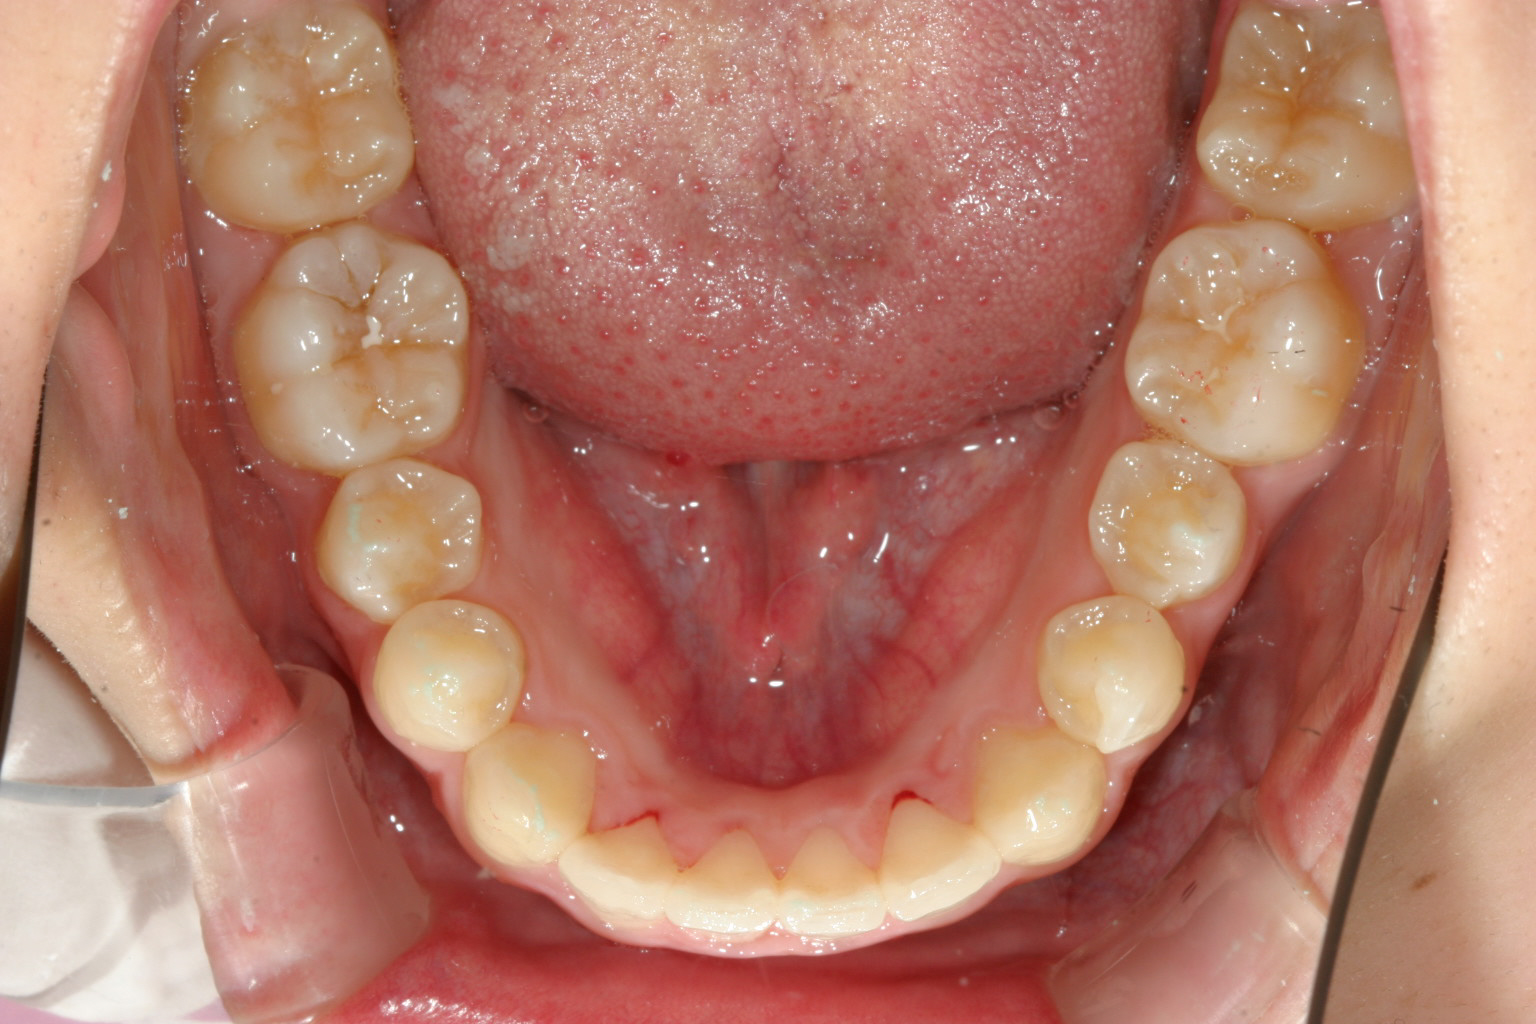

下顎も綺麗なアーチになりました。

上下の前後差が無くなりました。 綺麗なオーバージェットです。

今回のケースはアーチが尖っていた為に上下の前後差が出来、又尖った為に歯が前方に飛び出した感じ(出っ歯)になっていました。

この様なケースの場合アーチをU字に改善するのと同時にIPR(歯と歯の隙間を少し削る事)により前突感を改善致しました。

通常のワイヤー矯正だと先ず歯を抜く事から始まるのですがインビザラインはデジタル矯正ですから矯正以前に治療後の状態がシュミレーション出来る為、どこにどれだけの隙間を開ければどのようになるかと言う事が先に分かる為、抜くか抜かないかの判断が容易に出来、通常の抜歯矯正になるケースの半分以上が非抜歯で終える事が出来ます。